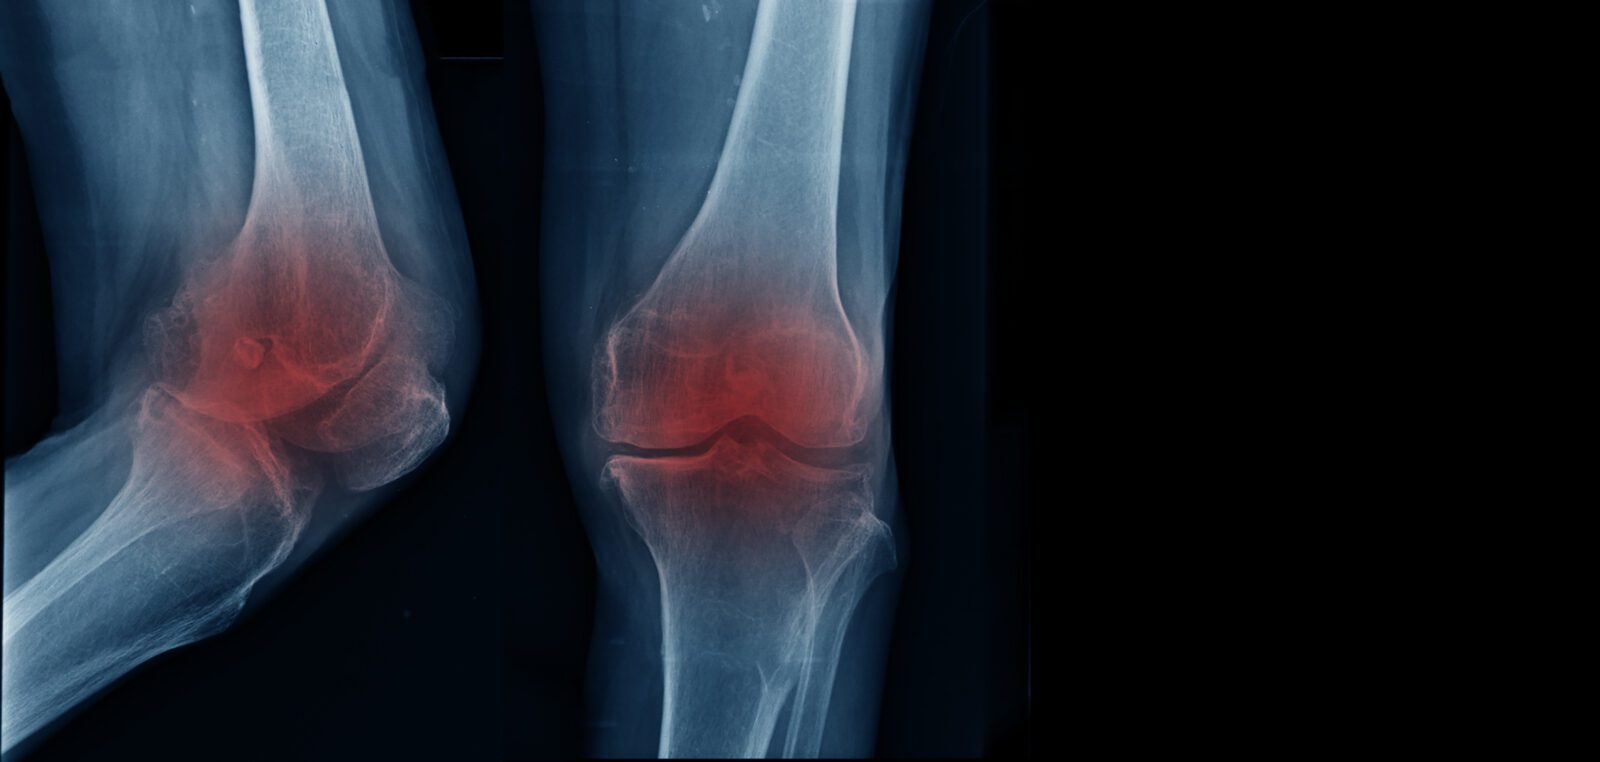

Röntgenfoto’s

Een röntgenfoto van de knie wordt gebruikt om de ernst van artrose in het kniegewricht te beoordelen. Dit gebeurt op basis van verschillende kenmerken:

• Gewrichtsruimtevernauwing

Dit kan optreden door verlies van kraakbeen en/of verschuiving van de meniscus. Een smaller wordende gewrichtsruimte kan wijzen op artrose.

• Botvergroeiingen (osteofyten)

Deze kunnen zich vormen als reactie op artrose. Osteofyten zijn extra botgroei die het gewrichtsoppervlak kunnen vervormen.

Daarnaast worden röntgenfoto’s ook gebruikt om de structuur van het bot onder het kraakbeen te beoordelen, de botarchitectuur.